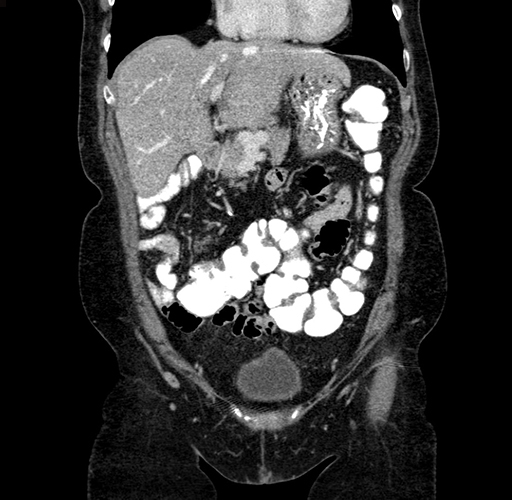

Axial Venous